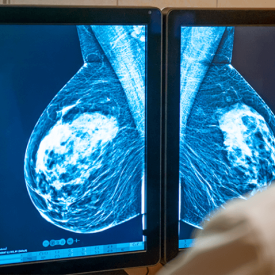

Insurance Companies Could Be Required to Cover Additional Breast Cancer Screenings for Women With Dense Breast Tissue

The new bills would impact an estimated 50% of Wisconsin women, whose breast tissue is white– just like possible tumors.